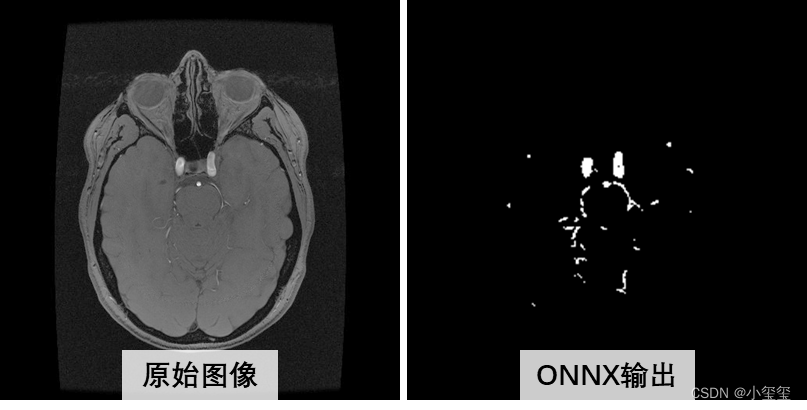

整个流程的演示我以医疗应用为背景,基于UNet完成训练、量化、部署整个流程。PS:之前想以细胞分割来展示,但是GT视觉效果比较密恐,所以找师弟要了一套看来舒服一点的医疗数据集重新训练更换效果图。

- 数据集来自2022年发表在TMI的论文《Attention-Assisted Adversarial Model for Cerebrovascular Segmentation in 3D TOF-MRA Volumes》。数据集实际上是MRA图像,我这里只保留了脑血管GT,用二分类的Unet来介绍整体的部署流程(这里感谢诺师弟的帮助)。

③ ONNX推理验证。到这里三个关键输出项都已经处理完成,这时候基于ONNX进行推理来验证这些项的有效性。代码细节见detect_onnx.py,在torchdnn的根目录下执行python demos/unet/detect_onnx.py。

执行完代码之后,得到ONNX结果,看起来没啥问题,可以进行阶段2的相关数据转换了。

从下图可以看出,量化ONNX的推理结果和原始ONNX推理结果,主体上是相似的,局部有细微的差异(量化必然存在或多或少的精度损失,大部分情况下是可用的)。